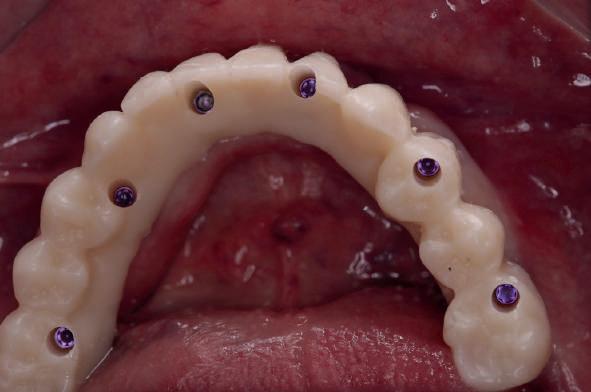

In the maxillary case, the implants with integrated MUA Abutment (monoimplantes fixo . oxy italia) are placed and scanning is performed before extractions of the remaining teeth that will serve as a reference for the scan and the position reference in the design software.

Once the surgical guide is stabilised, the osteotomies and placement of the lower posterior implants are performed, while the length of the anterior implants is changed in the drilling sequence according to the modified offset, which corresponds to the mounter, colour-coded according to the length of the offset.

Immediately after implant placement, the MUA Abutments are placed (Dynamic Abutment Solutions)

The immediate prostheses are milled in PMMA and fitted on their corresponding bases, adjusted and radiographically checked for proper seating.